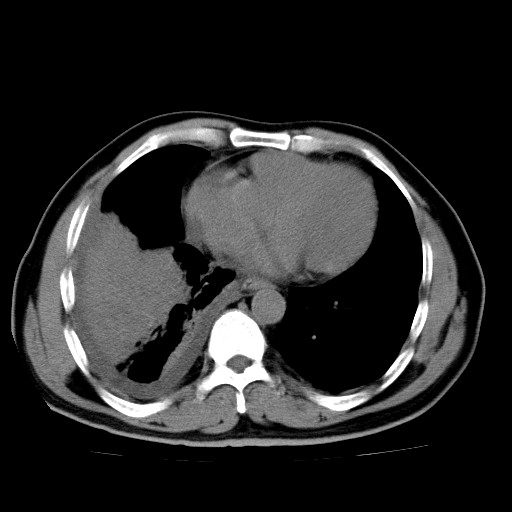

男,54岁,咳嗽,右侧胸痛10天。肺窗>150k,传不了

右肺中心型肺癌并右下肺不张,右侧胸膜纵隔转移。

右中央型肺癌并右肺下叶不张,纵隔内及右胸膜转移,右胸腔积液

考虑   右肺癌伴右下肺部分不张,阻塞性肺炎,纵隔淋巴结增大,右侧胸腔积液其他待排

考虑右肺下叶中央型肺癌并右肺下叶不张,纵隔淋巴结内及右胸膜转移。建议增强。

右下叶大片实变,肺门未见明显肿块影。有胸腔积液和纵隔内肿大淋巴结影。没有增强和肺窗,不好定。

考虑:1、右下叶周围型肺癌伴胸膜、纵隔淋巴转移?